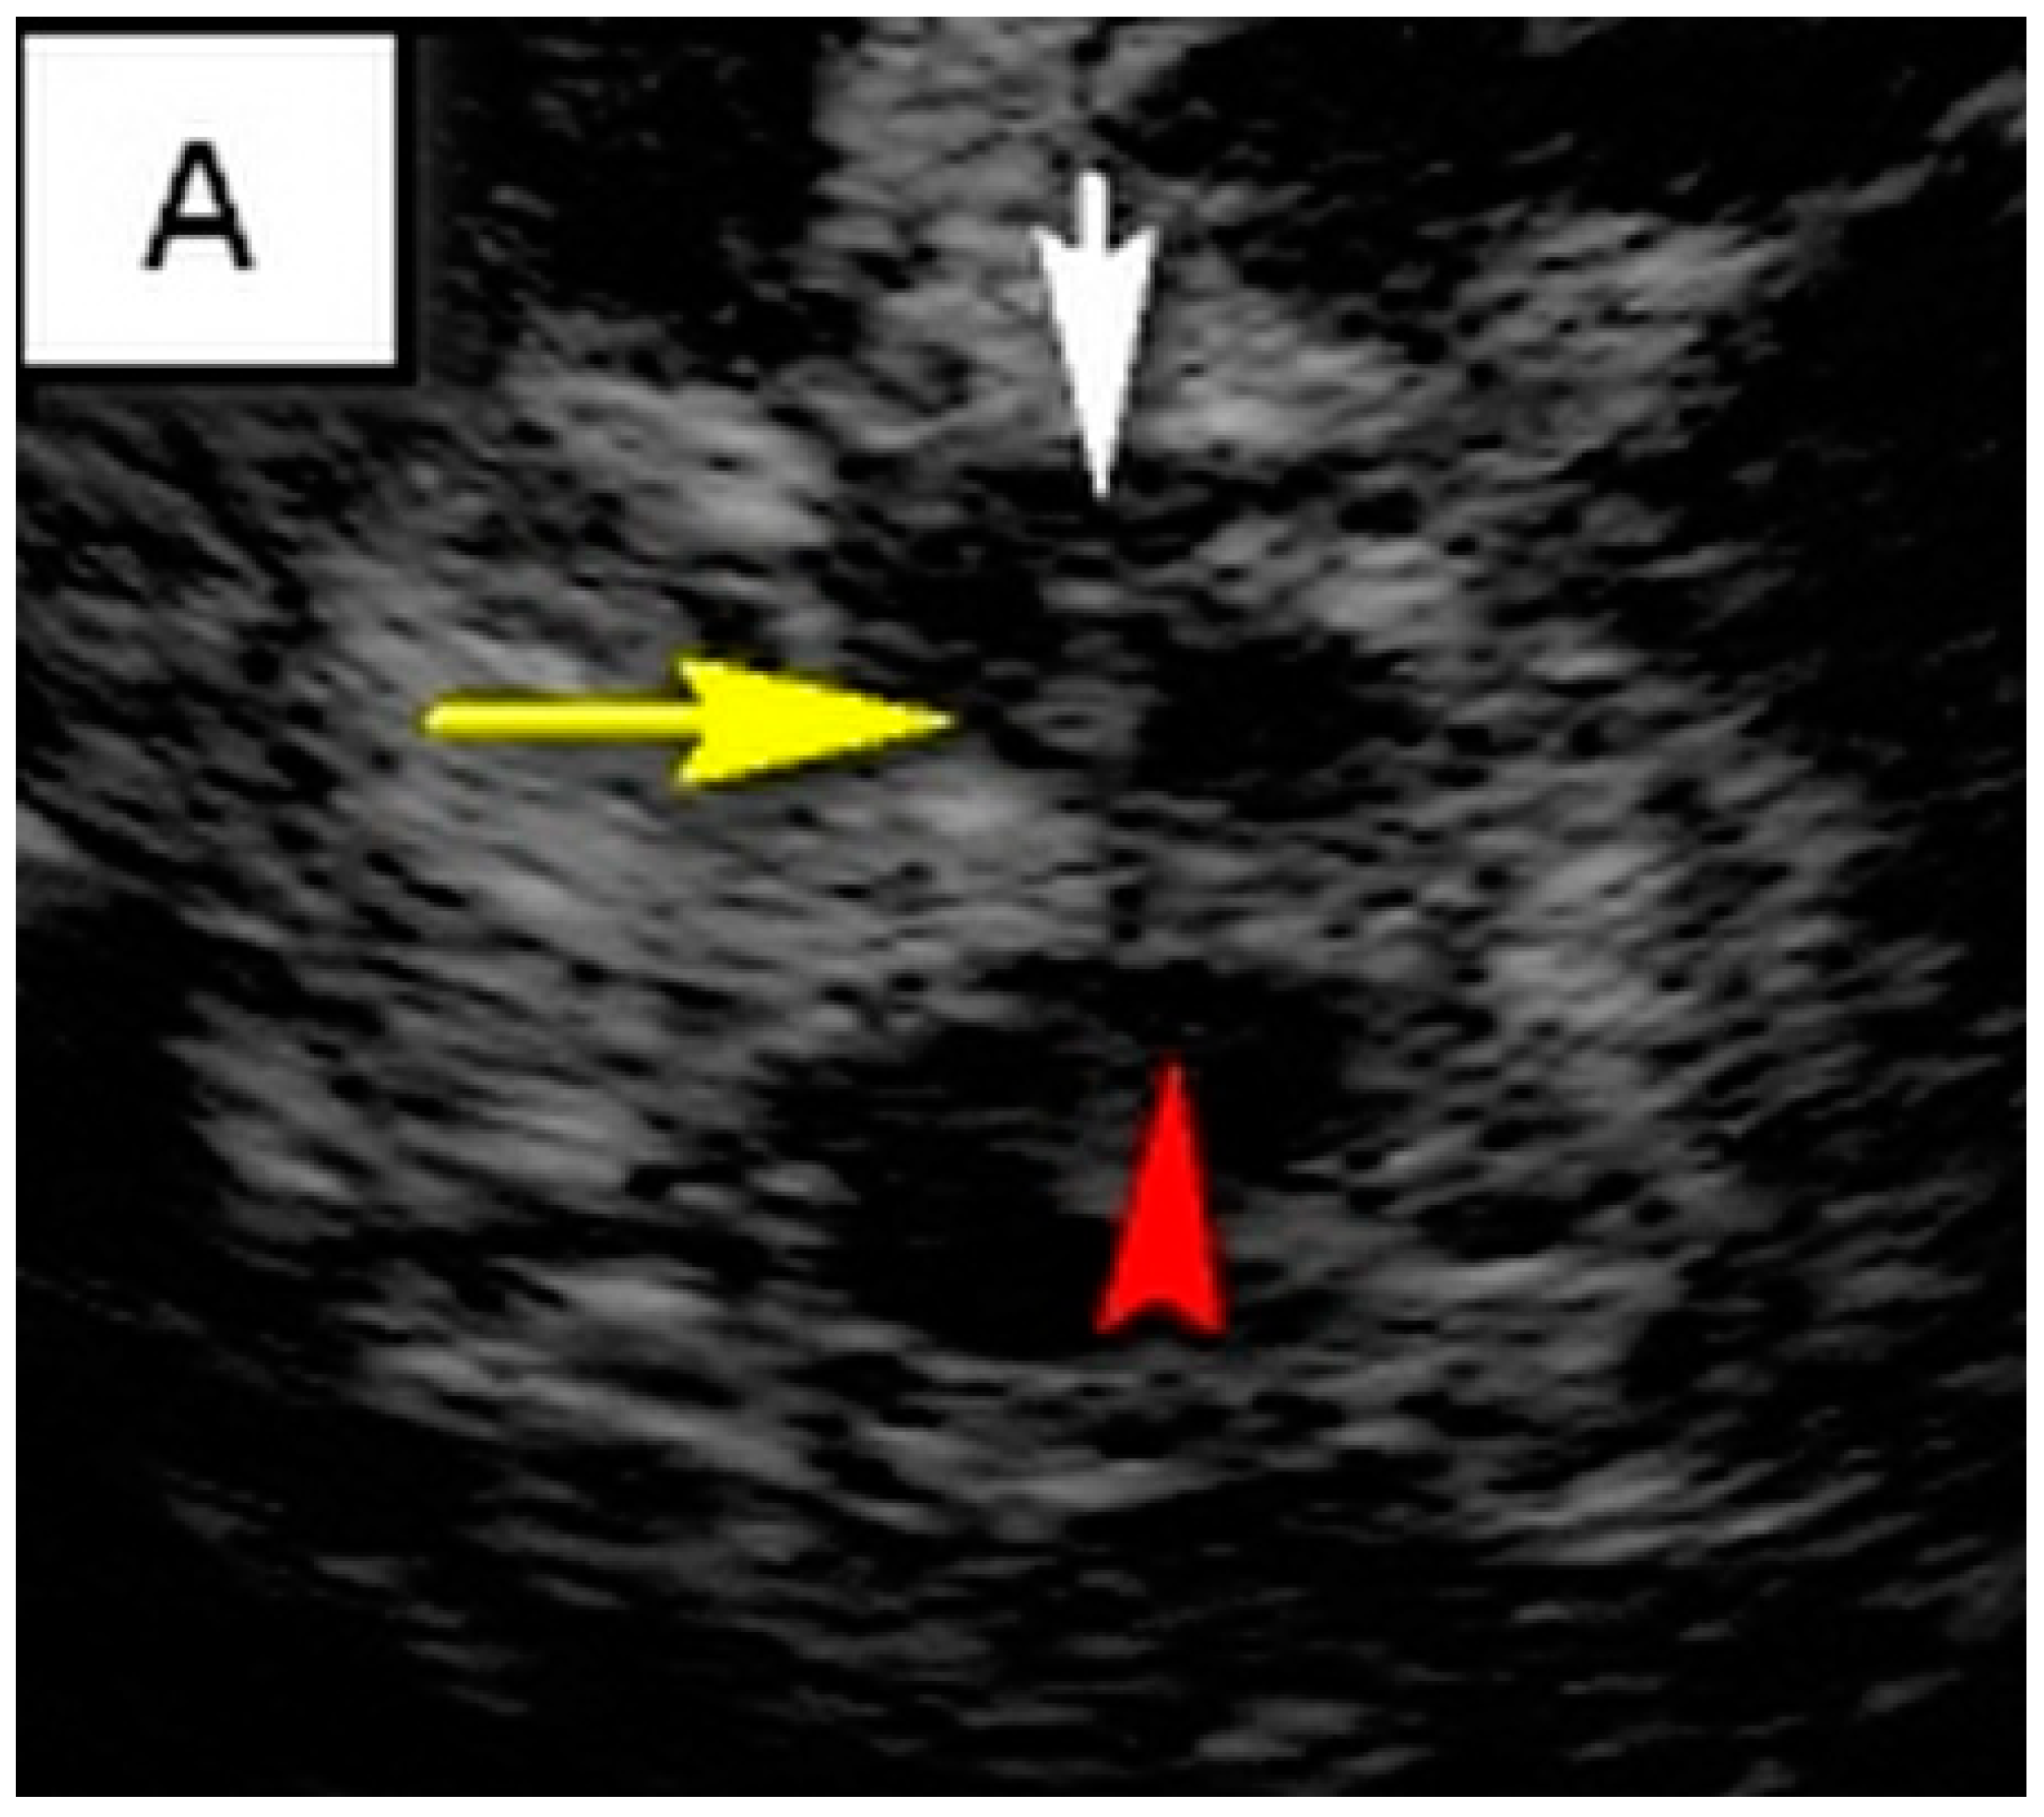

TCS characteristics of interest in our study are illustrated in Table 2. The control subjects consisted of 31 healthy controls, of which there was a slight female predominance (54.8%). The mean age of control subjects was 45.7 ± 11.6 years. The brainstem raphe was discontinued in 33.8% of patients. The SN hyperechogenicity was identified in 79.7% of patients, which represented a significant pathological finding, Figure 1. Third ventricle enlargement (over 6 mm) was present in 79.7% of patients, which can be attributed to gross (whole) brain atrophy, Figure 1. The fourth ventricle was enlarged in 45.9% of patients, which can directly be attributed to the atrophy of the cerebellum and its reduction in volume. The hyperechogenicity of other brain structures, such as the NR, the lentiform nucleus (NL) and the dentate nucleus (ND), is also illustrated in Table 2. We found a statistically significant difference in the hyperechogenicity of SN on the left and the sum quantitively, as well as in the frequencies of hyperintensity between patients with degenerative ataxias and the control subjects (p < 0.05). We have also found statistical significance in the difference between these two groups in the domain of the III and IV ventricles (p < 0.01). Results of mesencephalic atrophy are also presented in Table 2.

Figure 1.

(A) Butterfly-shaped hypoechogenic mesencephalic brainstem insonation level. Normal echogenicity of the brainstem raphe (highly hyperechogenic continuous line, same echogenicity as red nucleus; red arrow); dotted like highly hyperechogenic red nucleus (NR) (yellow arrow); normal echogenicity of substantia nigra (SN) (white arrow). (B) Butterfly-shaped hypoechogenic mesencephalic brainstem insonation level. Hypoechogenic interrupted raphe (red arrow); hyperechogenic substantia nigra (SN) (blurred yellow area, above 0.19 cm2). (C) Third ventricle level insonation depicted as hyperechogenic parallel lines. Normal diameter of the third ventricle (inner borders marked with red line). (D) Third ventricle level insonation depicted as hyperechogenic parallel lines. Dilatated third ventricle (12 mm, inner borders marked with white asterisk).

A positive and strong statistically significant correlation (p < 0.01) was found between dystonia and SN hyperechogenicity. Also, a positive and strong statistically significant correlation was found (p < 0.05) between rigidity and dyskinesia and SN hyperechogenicity. Such results are illustrated in Table 3. The higher SARA total score is statistically significantly correlated with the larger diameter of the III (r = 0.373; p = 0.001) and IV ventricles (r = 0.324; p = 0.005). Discontinued raphe was statistically significantly associated with Hamilton depression score (r = −0.225; p = 0.054). However, it must be said that it is a threshold value; that is, the level of significance is about 5%, so it can be interpreted that there is a negative and statistically significant correlation between the two mentioned variables.